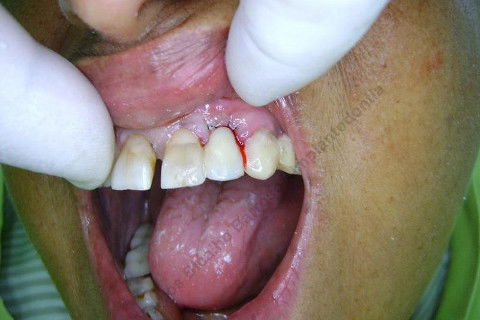

Paciente 66 anos, sexo feminino, procurou meus serviços para instalação de implante e coroa sobre implante na região do dente 22 com fratura radicular. Existem indicações para mais implantes mas a paciente está inrteressada no momento pela resolução deste caso.

Fotos do caso